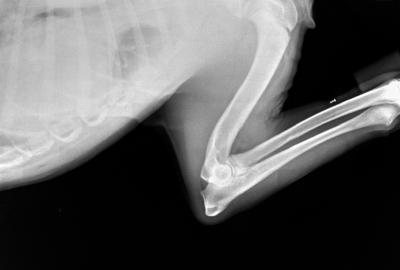

RTG Osteochondrózy (OCD)